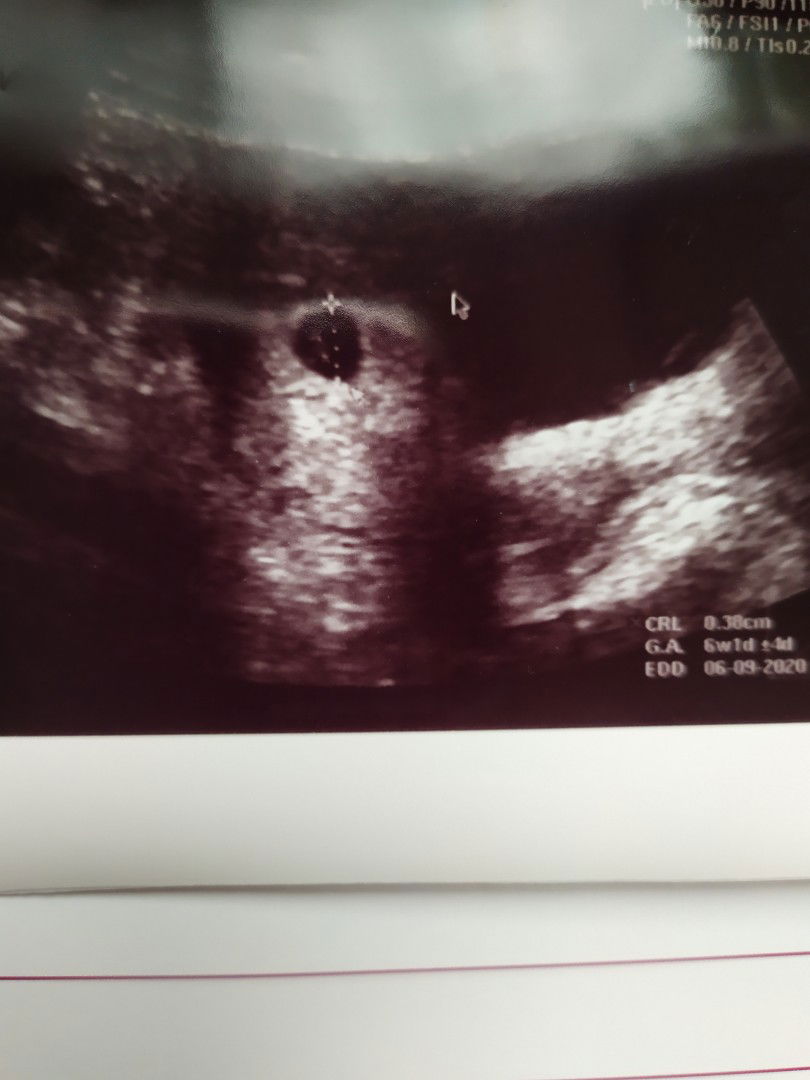

kantung lebih besar